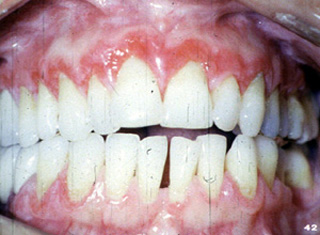

| A menudo

envuelve la encía y tiene una apariencia eritematosa y descamativa. Si

uno mira esta fotografía clínica, pueden verse áreas estriadas

blancas en la unión de la encía marginal con mucosa alveolar.

| Esta mujer 45

años de edad presenta úlceras

dolorosas de la encía alrededor de los dientes maxilares. El examen clínico

reveló la encía eritematosa con áreas

de ulceración. La higiene oral del paciente era buena y no había

evidencia radiográfica de enfermedad periodontal. No hay vesículas y ampollas; la piel no estaba involucrada. Esta condición era de un año

duración. No parecía cambiar en severidad durante ese tiempo.